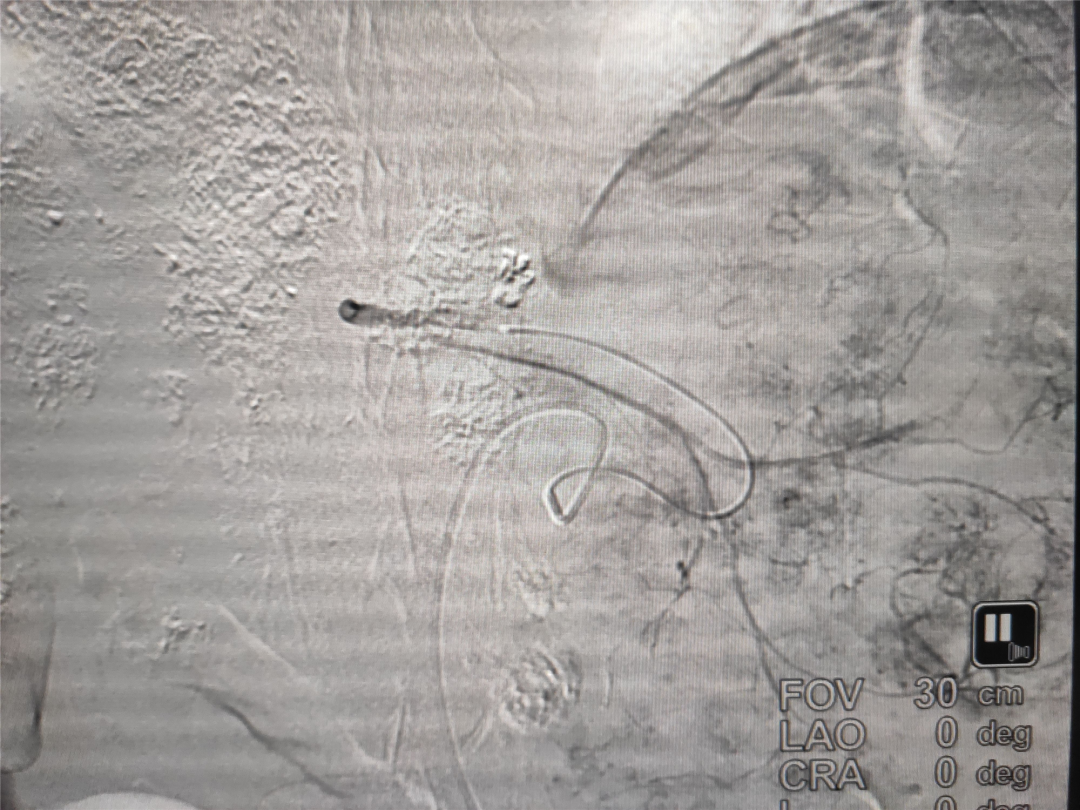

顶端手段丨丨寿光市中医医院成功完成我市首例载药微球栓塞治疗

王先生今年70岁,患有肝癌已经有3年时间,于2017年8月份行外科切除术。术后病理示:肝细胞肝癌,术后恢复可。于2017年11月、2020年7月、2020年10月行C-TACE (普通碘油栓塞)3次,患者栓塞术后无明显不适。于2020年12月份来院复查CT提示病变进展,经多方会诊,医院决定为王先生行D-TACE(载药微球栓塞)治疗。术中造影发现肿瘤供血血管迂曲并且血供丰富,医生应用CalliSpheres 1g+表柔比星50mg和适量碘油予以栓塞。

寿光市中医医院导管室主任李忠民介绍:这是我市第一例载药微球介入栓塞治疗肝癌。载药微球是指将化疗药物载于栓塞剂,在DSA指导下同时实现载药与栓塞剂的动脉递送,到达病灶后通过离子交换机制缓慢释放药物。其优点是能永久栓塞肿瘤血管而且不断地释放化疗药物,达到长期对肿瘤细胞进行栓塞和毒杀作用。D-TACE是治疗肝癌晚期患者新途径和栓塞治疗顶端手段,而传统栓塞剂栓塞完成后化疗药物被肝脏代谢,碘化油也会被肝脏消散,载药微球持续时间长,可达数月,且栓塞效果是永久的。